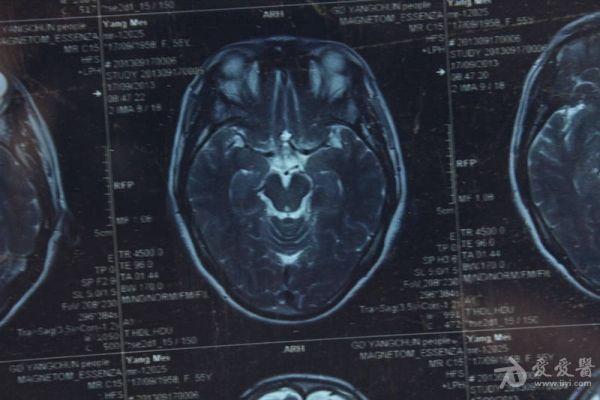

脑部占位病变CT,MRI图片,请帮忙诊断

最近感图样,无其它脑病病史

考虑脑膜瘤!!

磁共振没有平扫,增强矢状位没找到病灶。像脑膜瘤。

图片不是很清楚,应该是脑膜瘤!